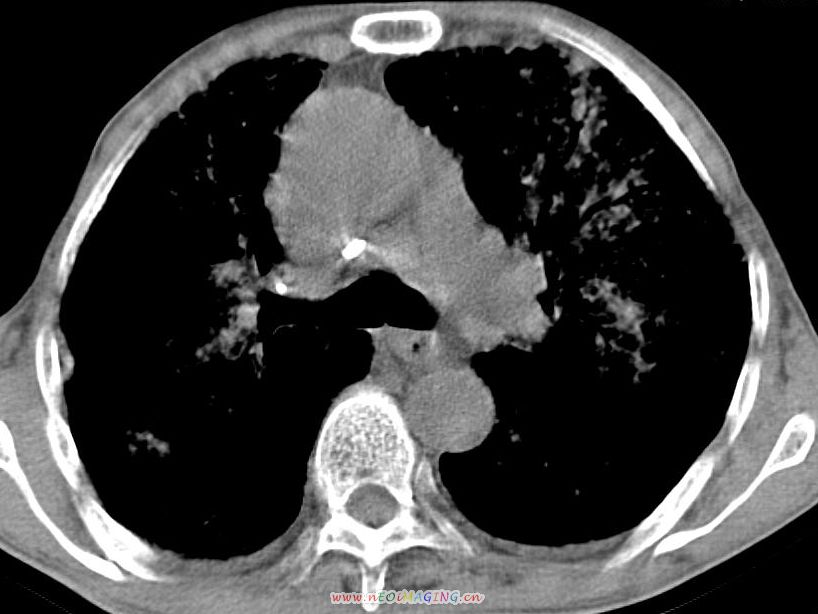

患者咳嗽月余,高热数天,咳黄色稍脓痰。

高热数天,咳黄色稍脓痰,肯定应该有急性化脓性感染,左上叶舌段及右肿叶可见多量斑片状及支气管气像,首先考虑肺部感染合并血型播散性肺脓肿(脓肿为早期改变),其次不排除有肺泡癌,第三不排除结核,建议治疗后复查

双肺野分布多个小结节状高密度影,其内散在斑片状模糊影,气管。支气管通畅,纵隔内淋巴结钙化,胸膜局限性增厚粘连,胸腔少量积液。结合病史考虑结核并感染的可能性大,胸膜炎并积液。肺泡癌待排。

亚急性血行播散型肺结核合并肺内感染

纵隔内见钙化的淋巴节,上肺见钙化灶,双肺均匀弥漫分布小结节影,边缘较清楚,能不能考虑是在矽肺的基础上并发的结核和感染,请详细了解病史结合临床.